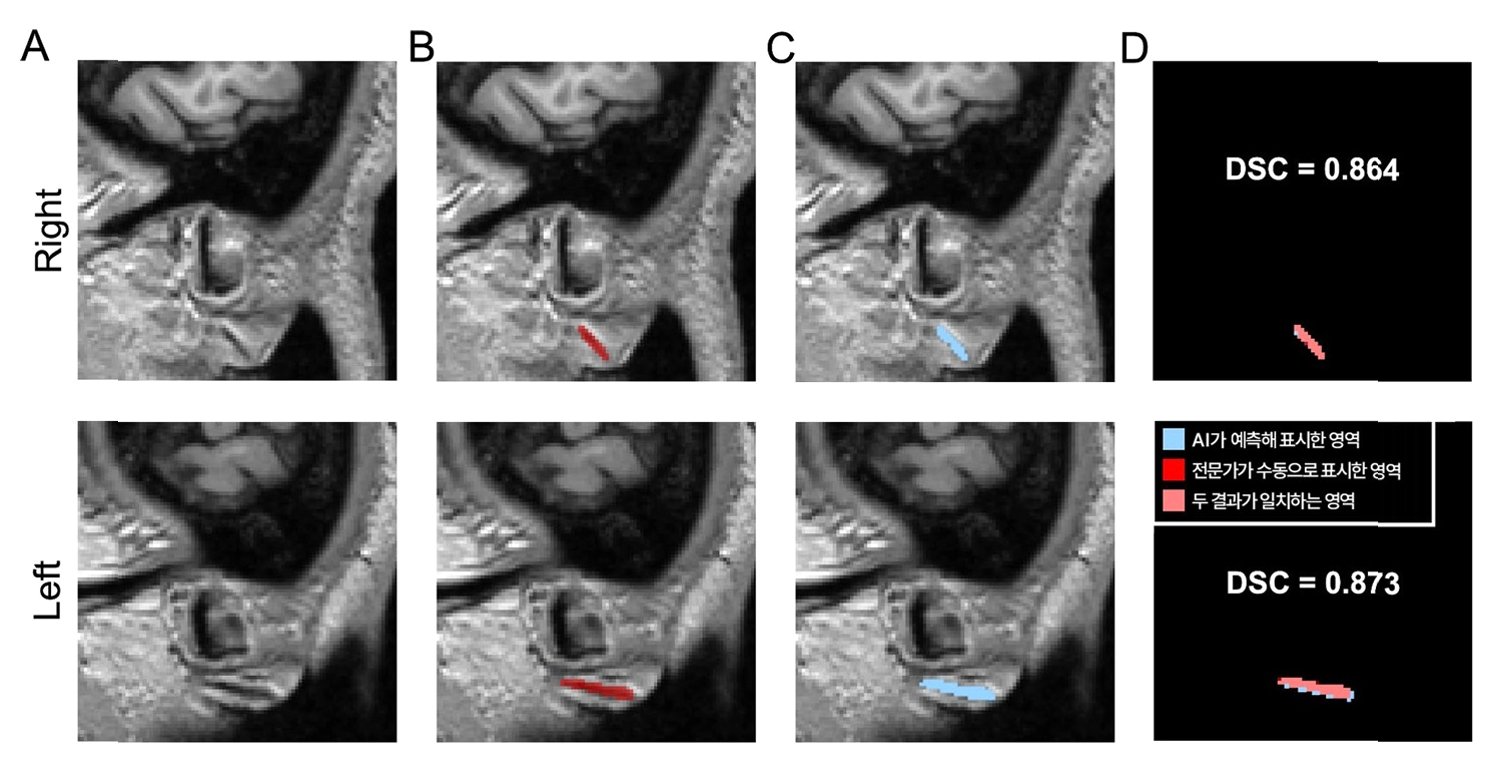

분당서울대병원 김기웅 교수팀은 3D 뇌 MRI에서 프랭크 징후를 자동으로 탐지하는 AI 모델을 개발했습니다. 이 모델은 전문가가 수동으로 표시한 프랭크 징후 영역과 AI가 자동으로 분할한 영역의 일치 정도를 측정하는 DSC값이 두 차례 검증에서 각각 0.734, 0.714로 나타나, 높은 정확도를 입증했습니다.

AI 모델의 정확도와 신뢰성

AI가 찾아낸 영역이 전문가의 판단과 70% 이상 부합한다는 뜻으로, 의료영상 분야에서 높다고 인정받는 수준입니다. 프랭크 징후의 유무를 얼마나 정확히 구분하는지 나타내는 AUC 값도 모두 0.9 이상을 기록했습니다.